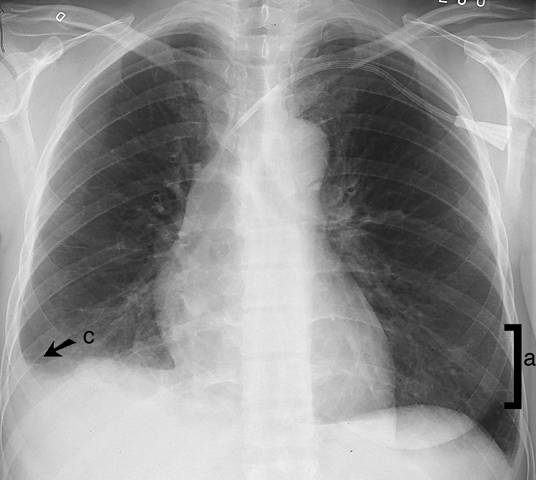

Kuva 1.

Interstitiaalinen ödeema keuhkoissa (sivukuva).

Ödeema kertyy myös lohkorajoihin (b) ja arpiin. Tilaan liittyy usein pleuraneste (c). Etukuva: ks.

«Interstitiaalinen ödeema keuhkoissa (etukuva)»